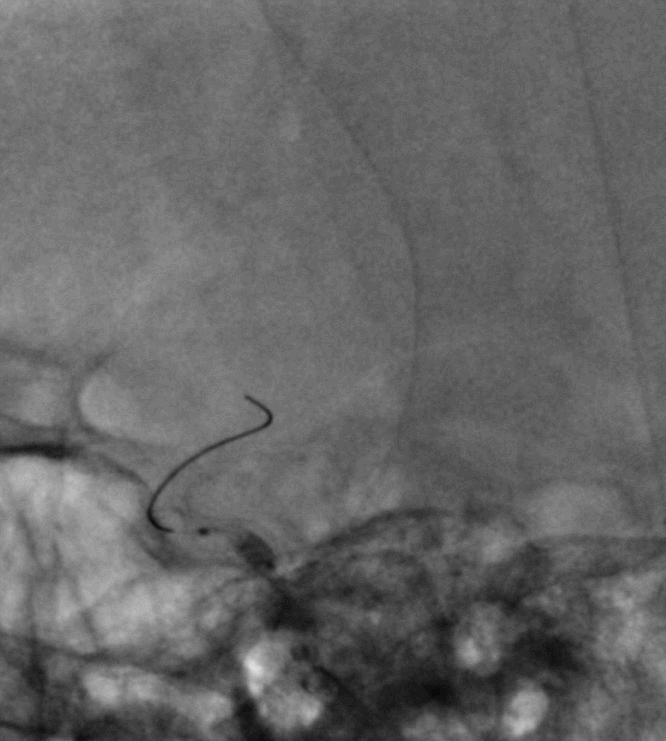

导丝成袢,继续“按摩”改善贴壁

“按摩”后再次造影,C2段狭窄仍较明显且贴壁欠佳